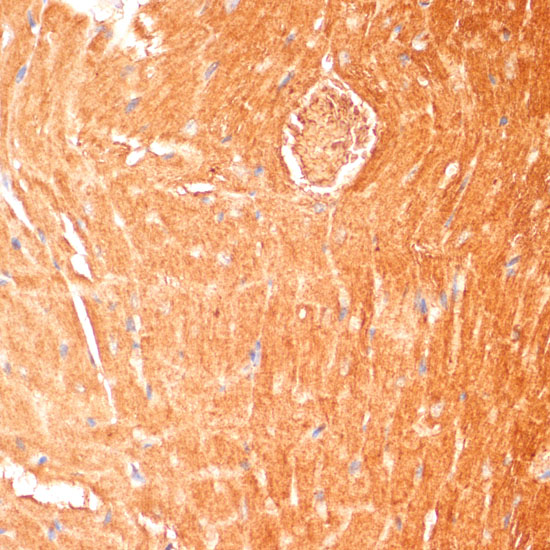

Immunohistochemistry of paraffin-embedded human colon using CPT1B antibody.

,

Immunohistochemistry of paraffin-embedded mouse heart using CPT1B antibody.